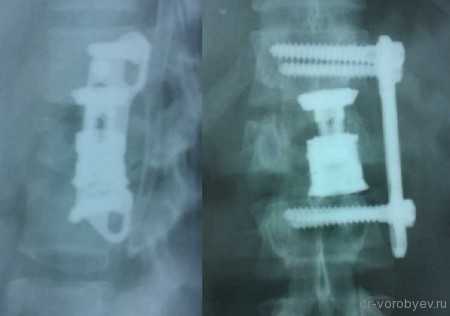

Перелом тела первого поясничного позвонка

Вид операционной раны. На место удаленного тела позвонка, после декомпрессии установлен протез тела позвонка Obelisk, Ulrich, Германия

Протез дополнительно фиксирован тораколюмбальной пластиной.

Рентгенологический контроль после операции.

Передний корпородез с использованием телескопического протеза тела позвонка Synex, фирма Synthes, США.